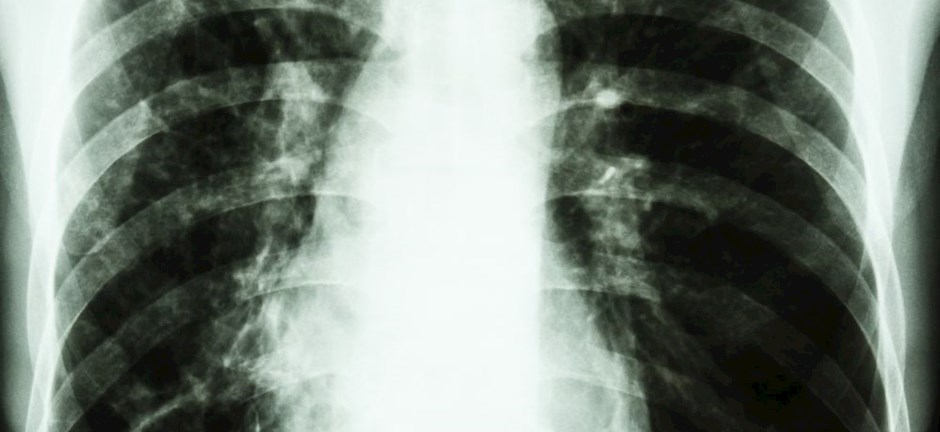

H φυματίωση αποτελεί μια νόσο με ισχυρή παρουσία και με σημαντική επίπτωση παγκοσμίως, με κύρια στόχευση τις χώρες με χαμηλό κοινωνικοοικονομικό status. To 2021 περίπου 10,6 εκατομμύρια ασθενείς νόσησαν από φυματίωση, με το 10% των ασθενών να είναι παιδιά.

Σύμφωνα με στοιχεία της επιστημονικής Ομάδας Εργασίας «Φυματίωση και Λοιμώξεις από Μη Φυματικά Μυκοβακτηρίδια» της ΕΠΕ, η φυματίωση ευθύνεται για περίπου 1,6 εκατομμύρια θανάτους παγκοσμίως μέσα στο 2021, αποτελεί την δεύτερη αιτία θανάτου από λοιμώδες αίτιο μετά τη λοίμωξη COVID-19 και την 13η αιτία θανάτου συνολικά. To 2021 περίπου 10,6 εκατομμύρια ασθενείς νόσησαν από φυματίωση, με το 10% των ασθενών να είναι παιδιά. Η πολυανθεκτική φυματίωση παραμένει μια απειλή για την δημόσια υγεία, καθώς πέρα από τις δυσκολίες στον χειρισμό της, μόνο το 1/3 των ασθενών είχε πρόσβαση στην κατάλληλη φαρμακευτική αγωγή μέσα στο 2020.